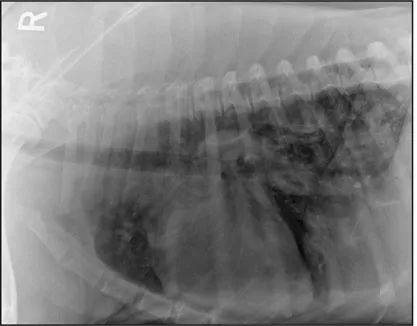

CASE 1.4 A 13-year-old spayed female mixed breed dog with a history of polyuria and polydipsia and abdominal distension. You obtain these thoracic radiographs: Fig. 1.4a, left lateral projection; Fig. 1.4b, dorsoventral projection.

1 What are your radiographic findings?

2 What is your radiographic diagnosis?

3 Are any additional radiographs needed?

1.4a

1.4b